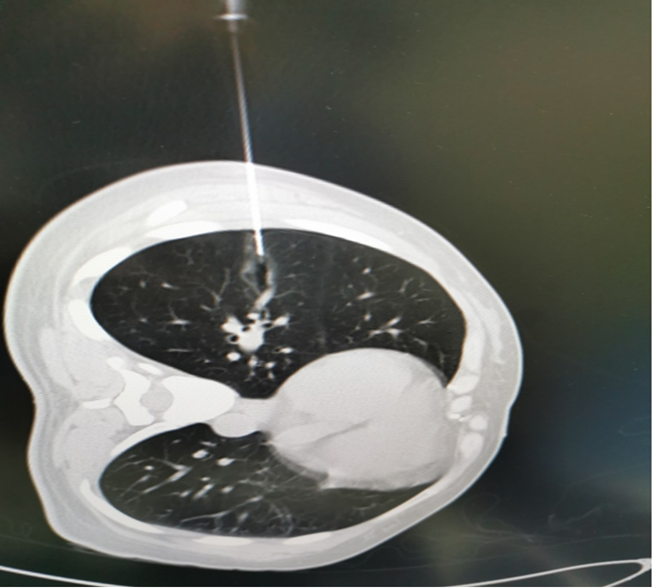

1.CT引导下经皮激光消融

适应症:适用于直径较小的肺结节(如磨玻璃结节、部分实性结节),尤其适合无法耐受传统手术或病灶位置复杂的患者。

操作方法:通过CT精确定位,经皮穿刺导入双波长激光光纤,逐层消融病灶并形成安全边界,全程影像实时监测。